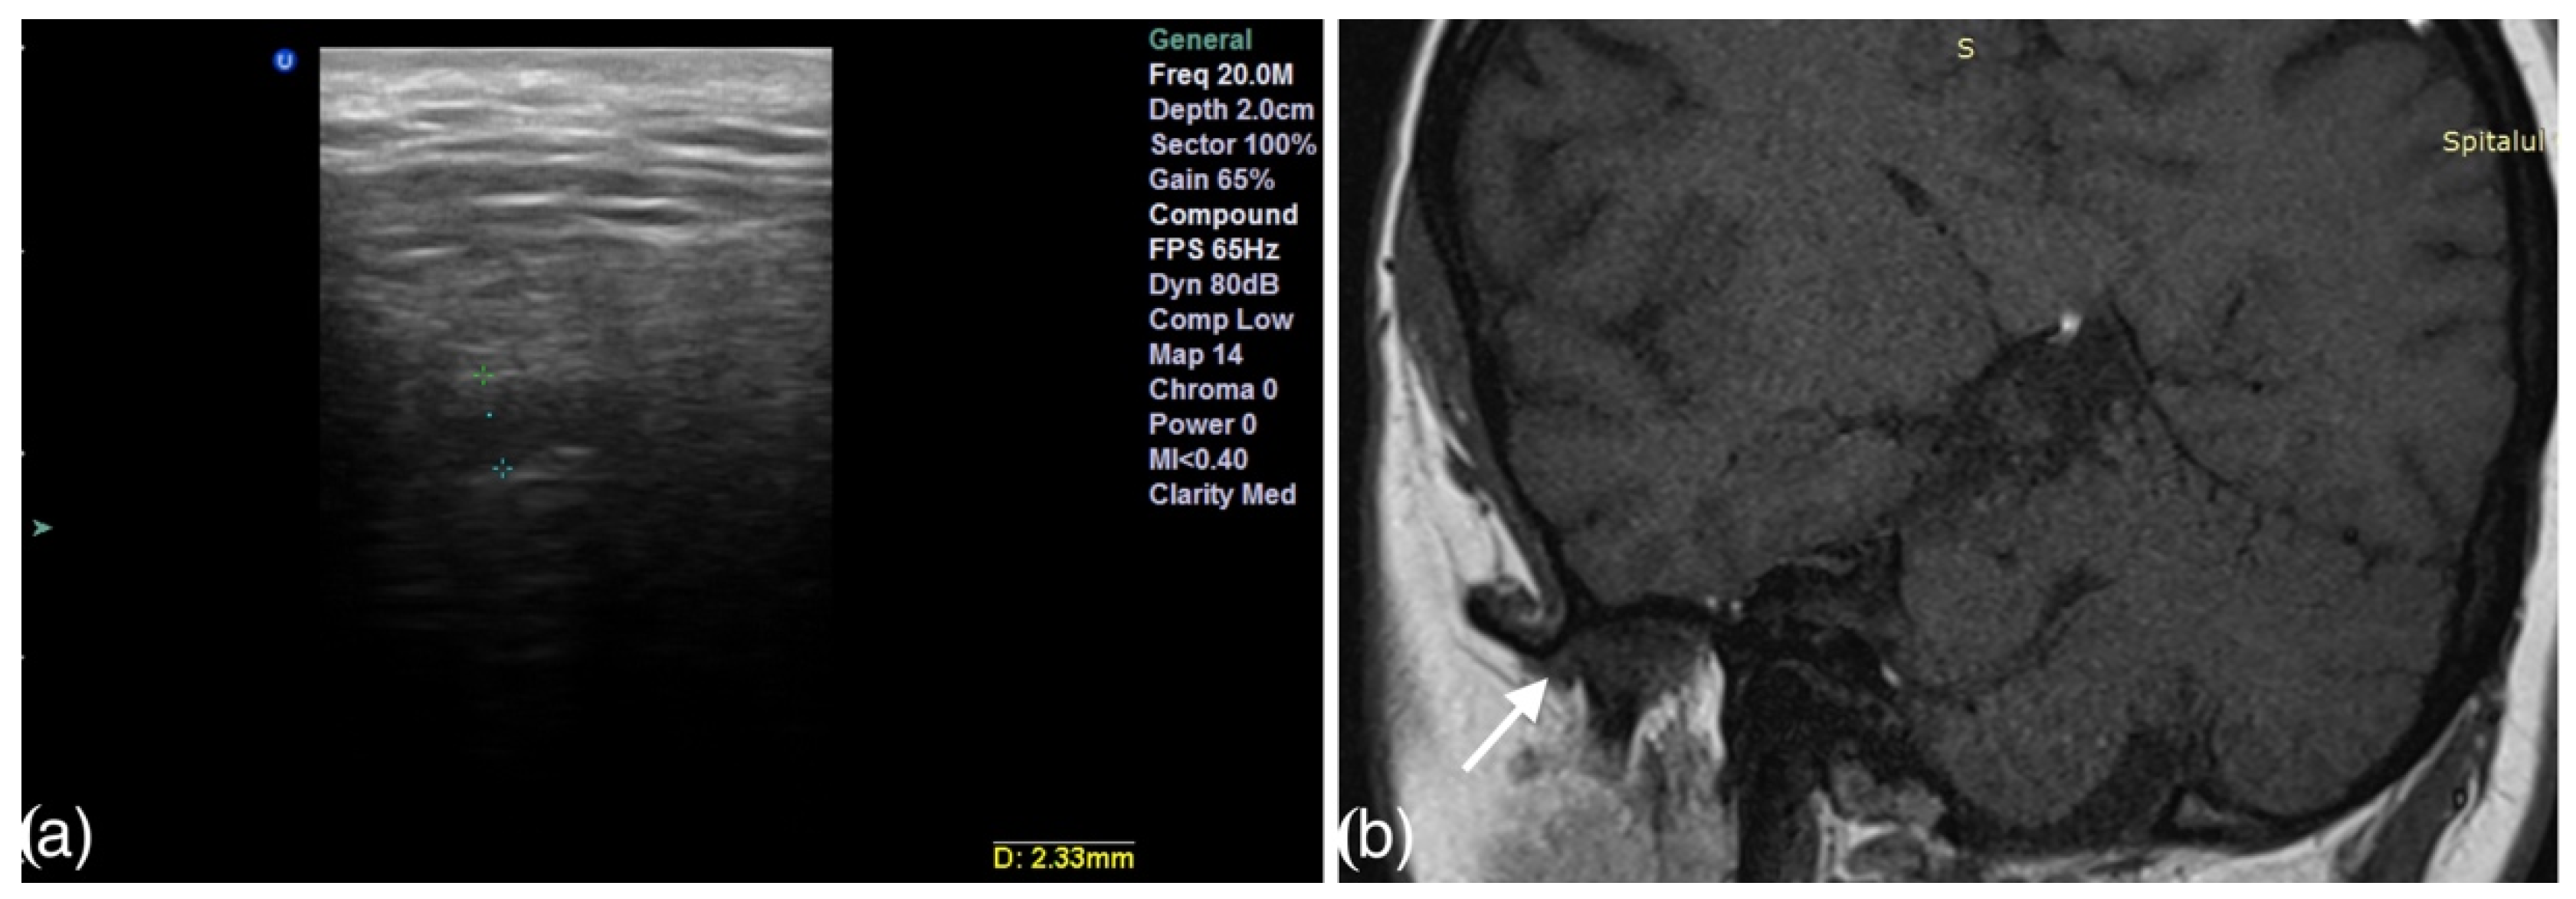

2.3. The Ultrasound Examination

- Talmaceanu, D.; Lenghel, L.M.; Bolog, N.; Stanila, R.P.; Buduru, S.; Leucuta, D.C.; Rotar, H.; Baciut, M.; Baciut, G. High-resolution ultrasonography in assessing temporomandibular joint disc position. Med. Ultrason. 2018, 20, 64–70. [Google Scholar] [CrossRef] [Green Version]

- Talmaceanu, D.; Lenghel, L.M.; Bolog, N.; Buduru, S.; Leucuta, D.; Horatiu, R. High-resolution ultrasound imaging compared to magnetic resonance imaging for temporomandibular joint disorders: An in vivo study. Eur. J. Radiol. 2020, 132, 109921. [Google Scholar] [CrossRef]

- Manfredini, D.; Tognini, F.; Melchiorre, D.; Zampa, V.; Bosco, M. Ultrasound assessment of increased capsular width as a predictor of temporomandibular joint effusion. Dentomaxillofac. Radiol. 2003, 32, 359–364. [Google Scholar] [CrossRef]

- Bas, B.; Yılmaz, N.; Gökce, E.; Akan, H. Ultrasound assessment of increased capsular width in temporomandibular joint internal derangements: Relationship with joint pain and magnetic resonance grading of joint effusion. Oral Surg. Oral Med. Oral Pathol. Oral Radiol. Endod. 2011, 112, 112–117. [Google Scholar] [CrossRef] [PubMed]